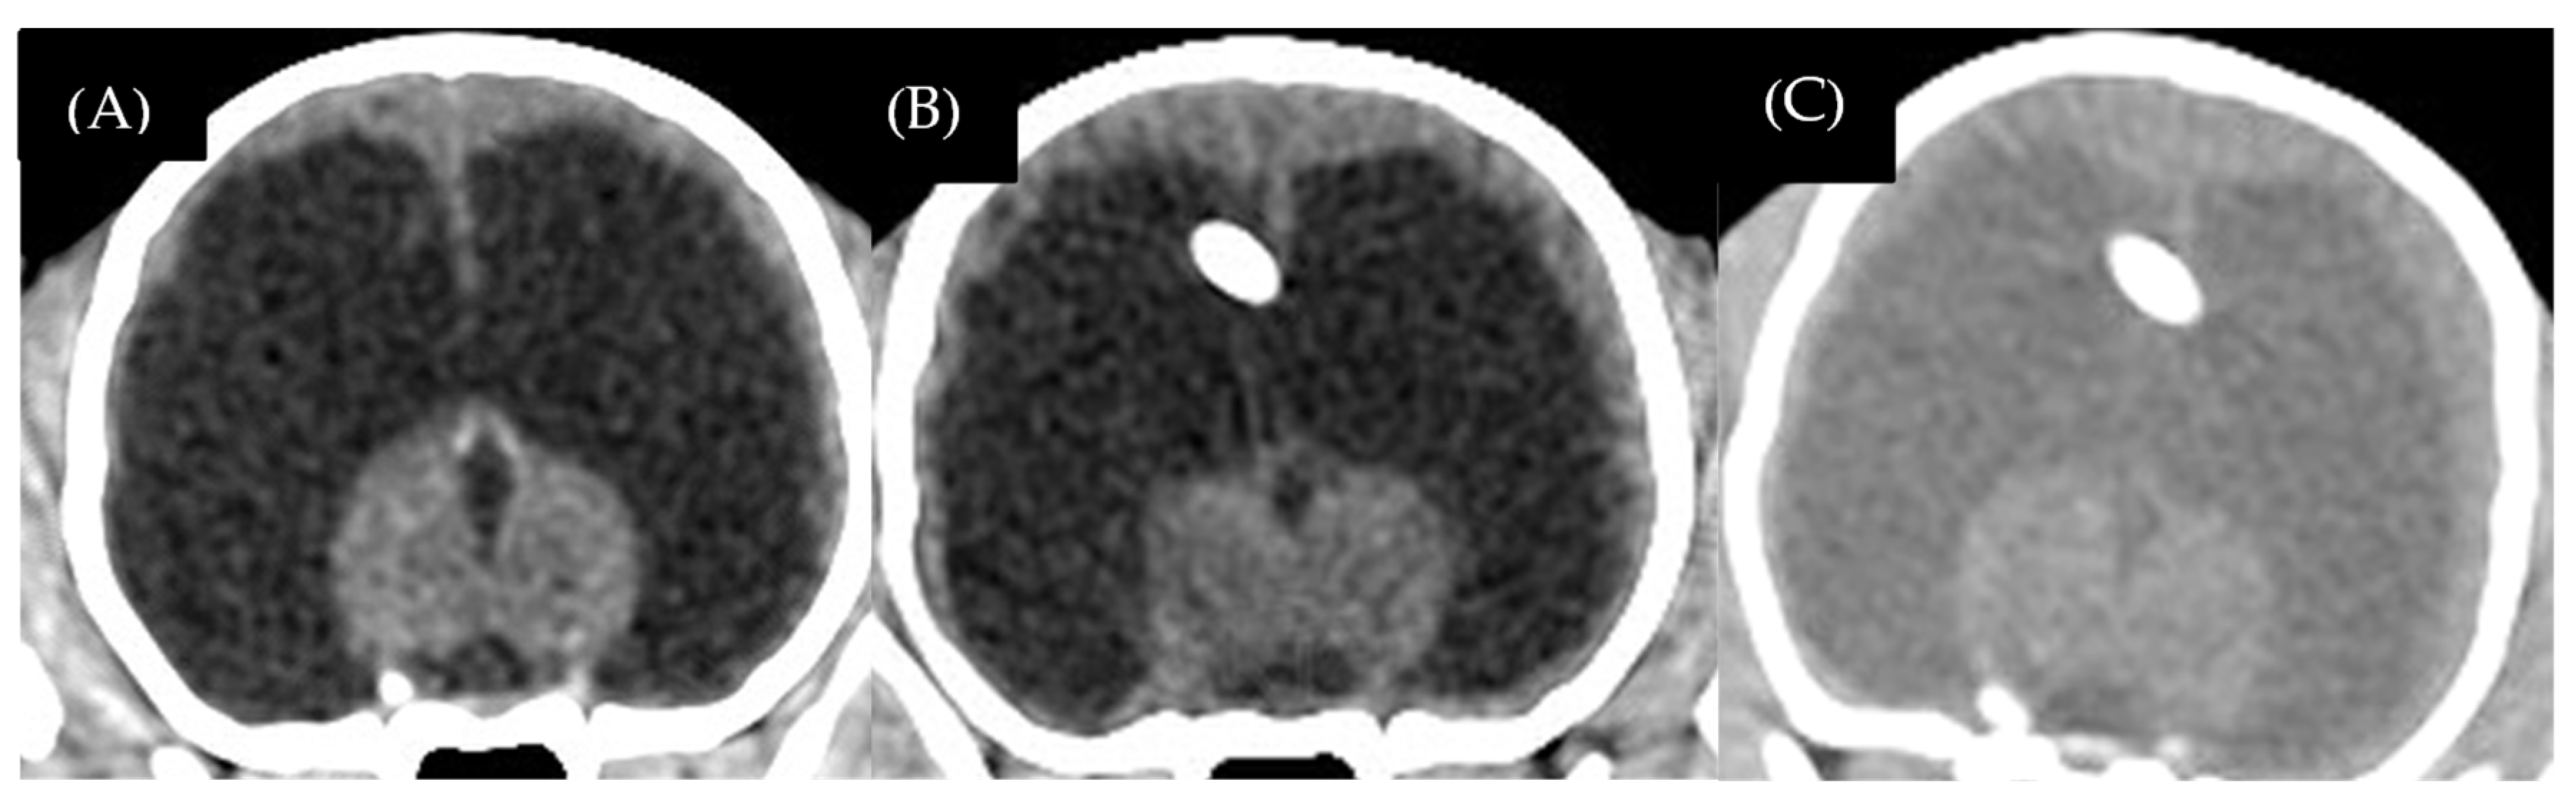

3.1.3. Complication

3.2.3. Complication

| 6 | Chihuahua | male | 5 | 1.4 | 6 | Obstruction of the lateral apertures with encephalitis | 8.80 | 49.70 | 45.30 | 8.85 | No detectable |

| 7 | Chihuahua | female | 48 | 2.5 | 48 | Obstruction of the lateral apertures with meningoencephalitis of unknown origin | 5.88 | 16.40 | 13.40 | 18.29 | No detectable |

| 8 | Chihuahua | male | 10 | 3.7 | 32 | Post-traumatic | 7.35 | 11 | - | - | - |